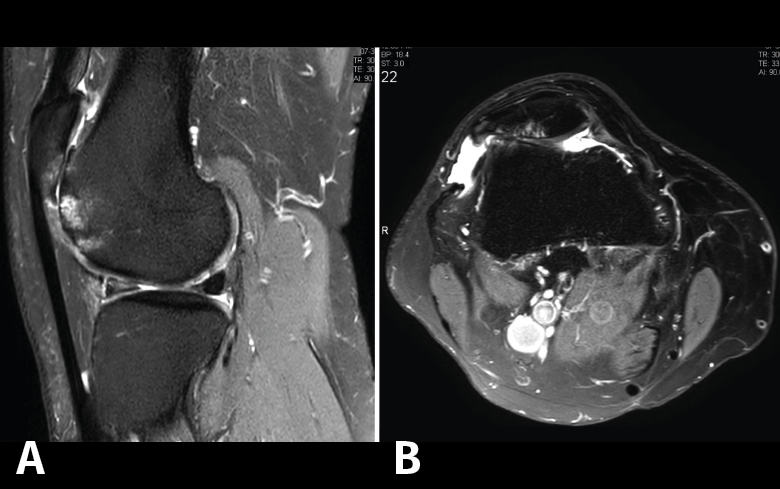

Figura 53. Corte de secuencia sagital (A) y axial (B) T2 Fat-Sat de RM de rodilla: lesiones osteocondrales en el fémur y la rótula.

Numerosos estudios demuestran la utilidad de la RM para definir la estabilidad o inestabilidad de la lesión en la osteocondritis, destacando su carácter no invasivo y la capacidad de valorar la progresión y la respuesta al tratamiento(21)(Figuras 53 y 54).